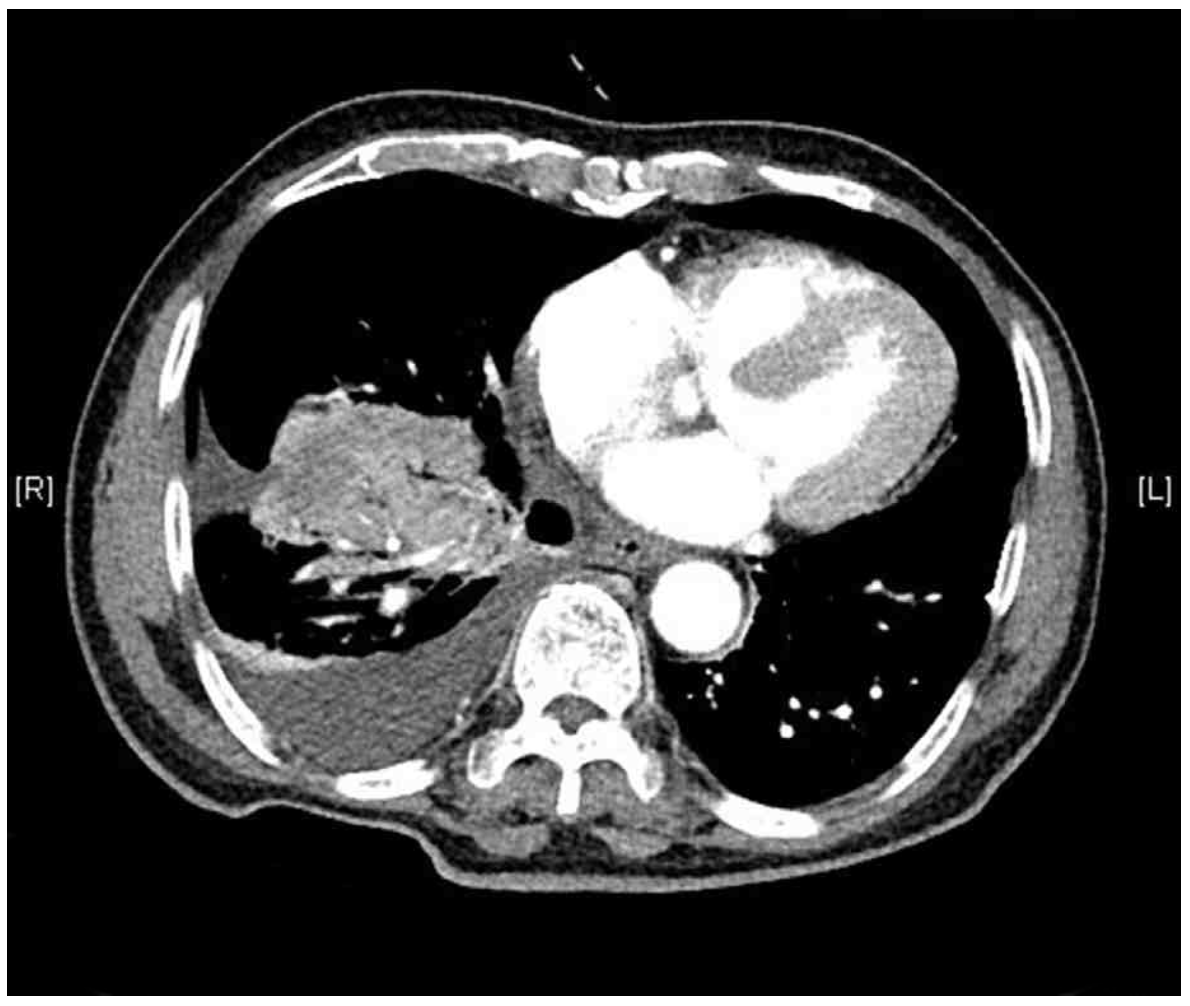

CT: RLL mass, Rt. pleural effusion

• CXR상 RLL diffuse opacity가 확인되며, 자세한 평가를 위해 실시한 Chest CT에서 거대한 mass와 Rt. pleural effusion이 관찰된다. Mass는 solid한 양상으로 irregular margin을 보이고 있으며 central necrosis가 의심되는 irregular enhancement의 소견이 관찰되는 바 폐암의 가능성이 높다고 판단할 수 있다.

• 따라서 조직검사를 통한 확진이 필요하며, 위 증례의 병변은 central airway에 인접하여 있으므로 기관지내시경을 통해 조직검체를 확보한다.